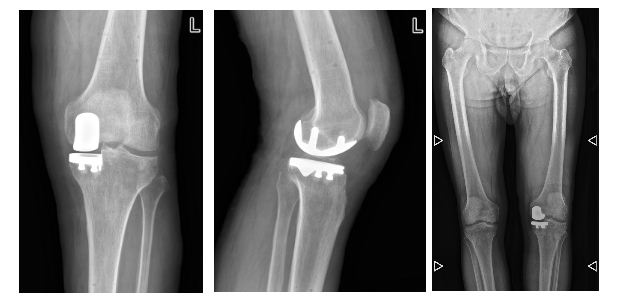

术后X-ray片。绵阳市骨科医院供图

借助先进的骨科手术机器人导航系统,为手术全程构筑起“智能安全屏障”。术前,突破传统二维影像局限,基于患者CT数据构建1:1的膝关节三维虚拟模型,手术团队可在虚拟空间中智能规划并模拟截骨角度、假体型号和安放位置,制定个性化的手术方案。

术中,机械臂在AI导航引导下,能执行0.1毫米级别的精准截骨操作,减少创伤;具备安全区间控制功能,为血管神经提供主动保护;实时监测膝关节的软组织张力和间隙平衡,动态调整计划,确保假体植入后受力均匀,增加假体使用寿命和术后关节活动度。